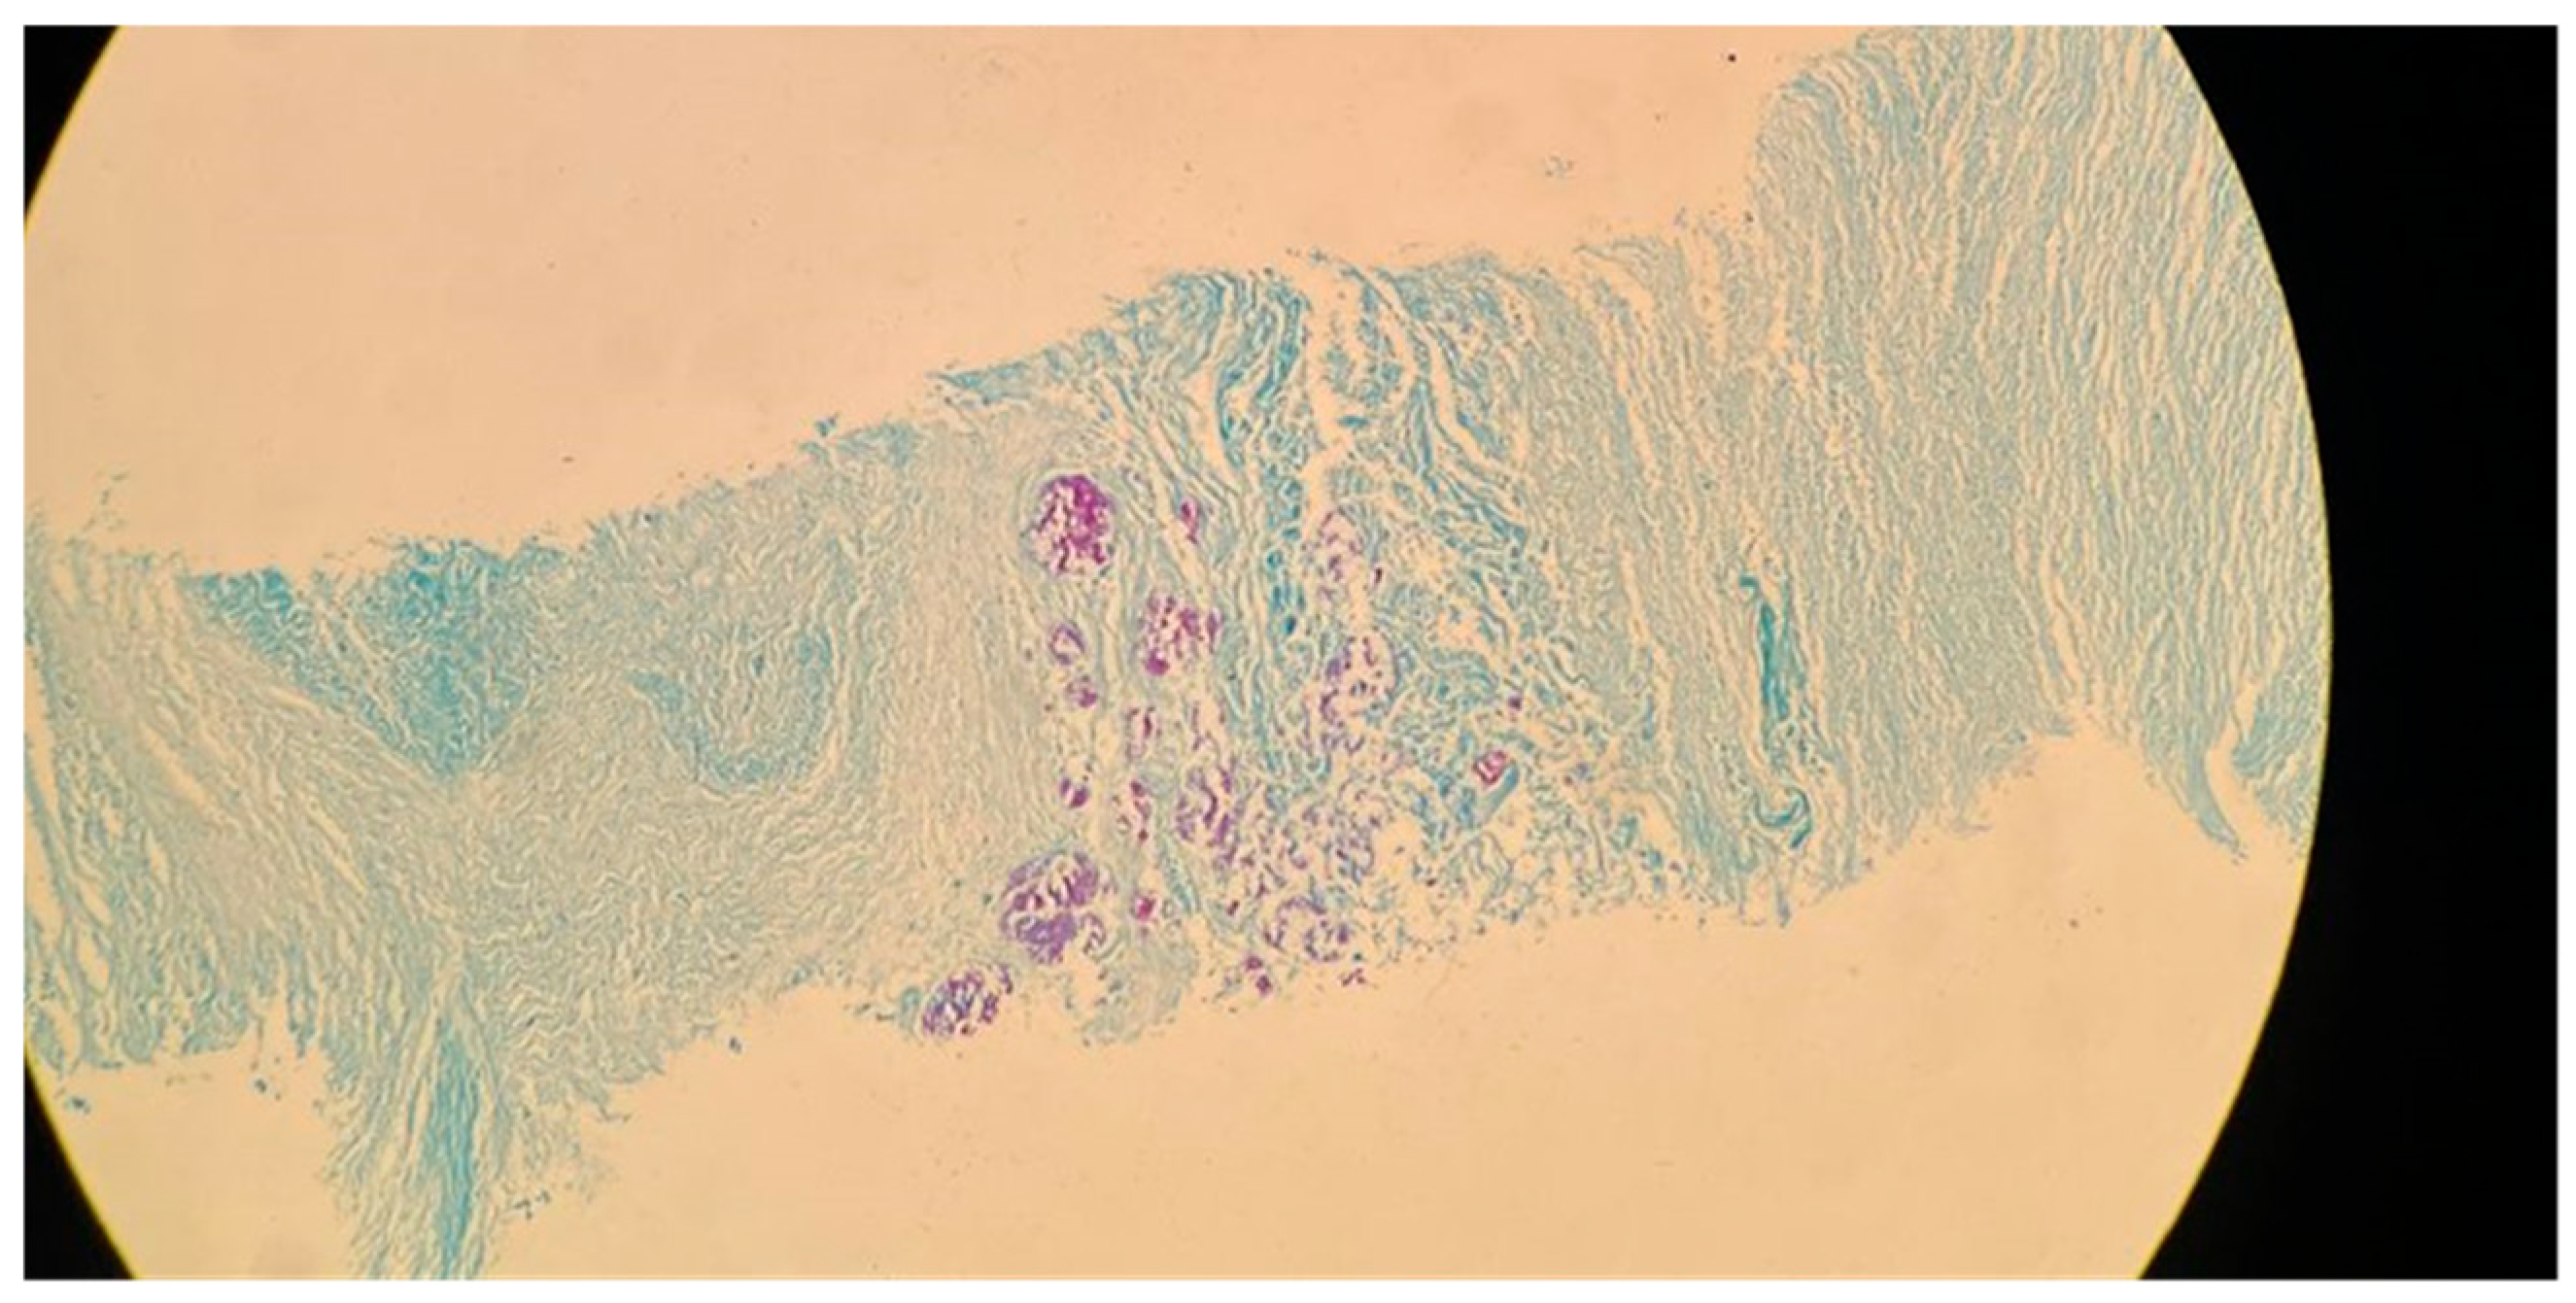

M. tuberculosis infection often leads to injury to the pleura. This includes the thickening and fibrosis of the pleura, and in many of these cases, patients further form calcification. About 40.9% of patients with fibrosis form these calcifications, as demonstrated in a CT-based study by Deshpande et al. [9]. The presence of fibrosis often results in decreased lung capacity on one side of the chest. This can be due to the cavities that form within the lungs as a result of the infection. In patients who had a single cavity in their lungs, fibrosis was found 100% of the time and calcification 80% of the time. In addition, 90% of these single cavities were found in the upper lobes of the lungs [9]. Upper lobe damage to the lungs can be seen in Figure 2. Further evidence of the presence of M. tuberculosis can be observed in Figure 3, in which many acid-fast bacilli are shown. The consistent presence of fibrosis and calcification in these cases suggests prolonged infection. This represents the host’s attempt to contain the mycobacterial focus. Fibrosis may contribute to disrupted lung structure and functional impairment of the lung, while calcification often marks the healing or inactive phase of a granulomatous lesion.

Figure 3. Acid-fast bacillus (AFB) staining of a sputum smear from the same patient referenced in Figure 2, demonstrating numerous acid-fast bacilli (red rods) against a blue background (100× magnification).